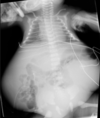

XR findings in ARPKD

Wide Abdomen

Bilateral flank “masses”

Pulmonary hypoplasia